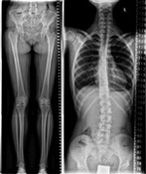

We are very satisfied with the image quality for both, spine and legs, when we use the stitching feature at the CombiDiagnost R90 table."